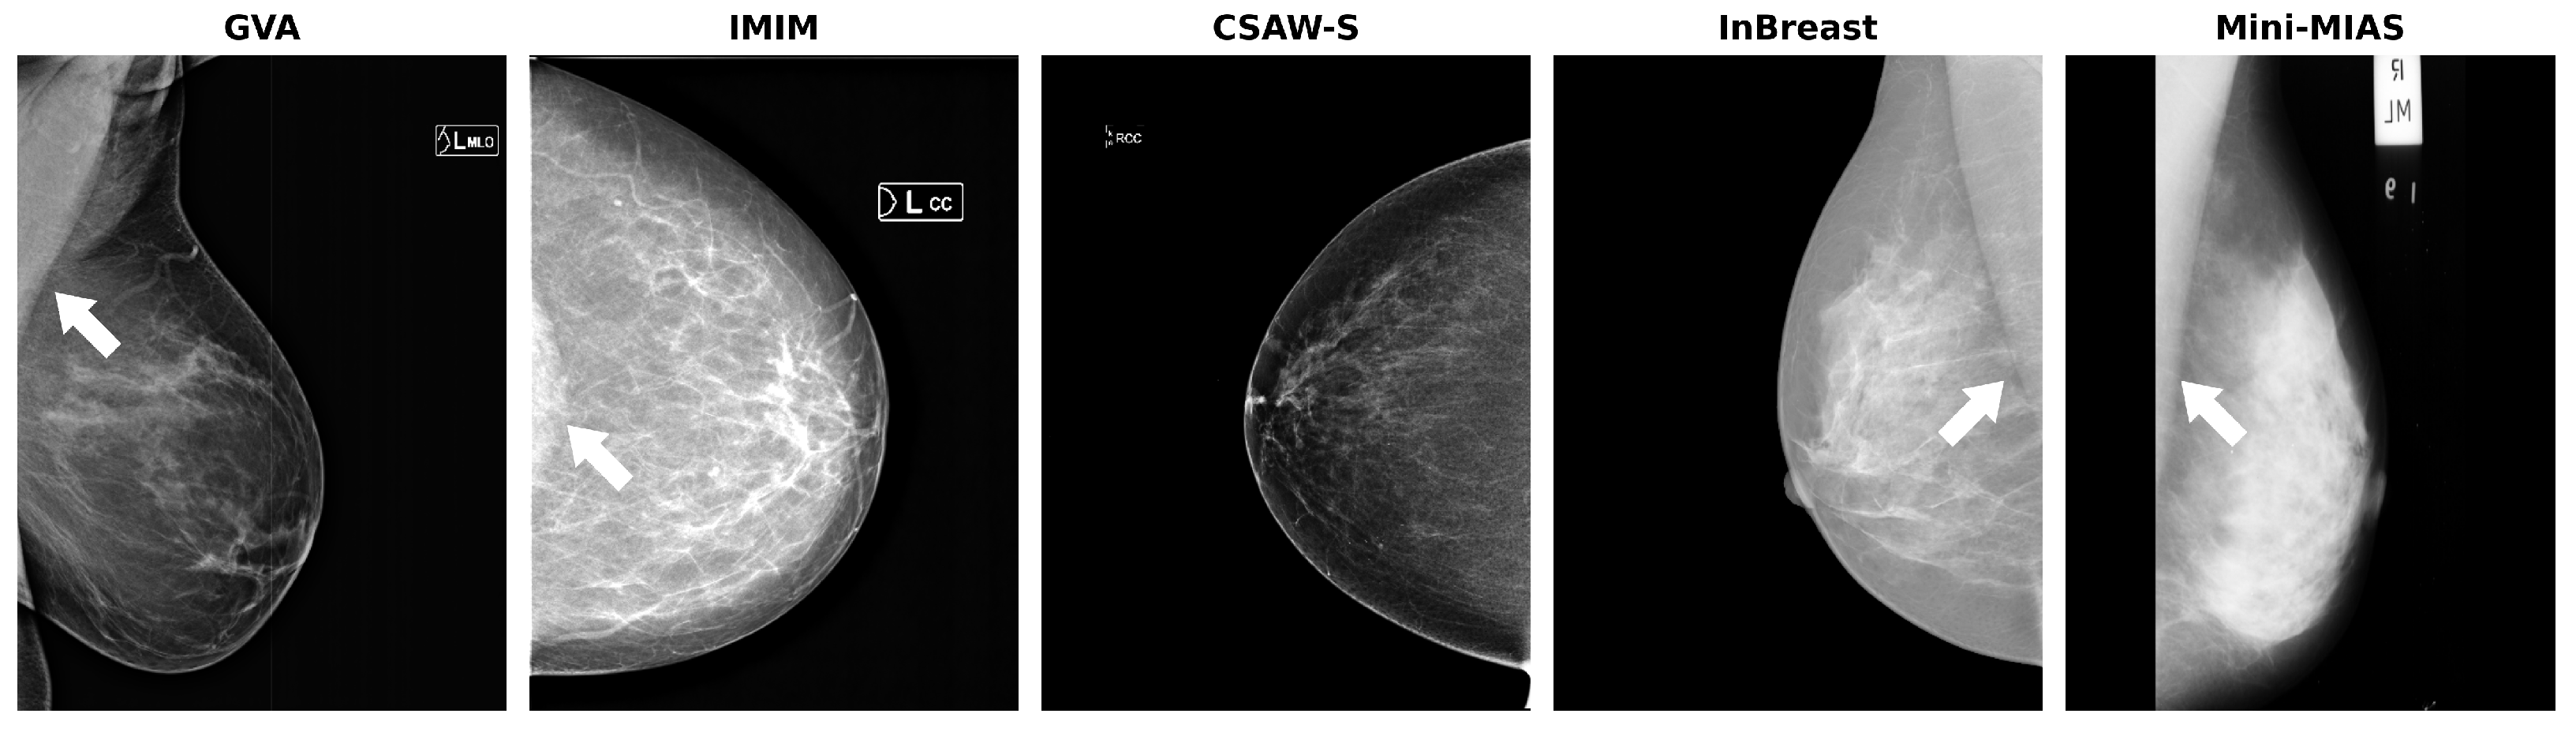

- GVA (proprietary): A multi-center dataset that covers 11 medical centers of the Generalitat Valenciana (GVA) as part of the Spanish breast cancer screening network. It includes 1785 women with ages from 45 to 70. The CC and MLO views were available for 10 out of 11 of the centers, while one center only collected the CC view. This dataset was used for training, validation, and testing. The dataset was randomly partitioned into 75% (2492 mammograms) for training and validation (10%) and 25% for testing (844 mammograms). All the mammograms are of the type “for presentation”. Further details about this dataset can be found in our previous work [9].

- IMIM (proprietary): A dataset composed of 881 images obtained at the Hospital del Mar Research Institute (IMIM). It was included solely for testing purposes to better evaluate the generalization performance of the models. This dataset consists of images from three different acquisition devices. One of these devices (Hologic Lorad Selenia, Marlborough, MA, USA) is older and was used to obtain images back in 2012. As a result, the image quality is lower, making the segmentation task more challenging. Only CC views were provided for this dataset, and they are also of the type “for presentation”.

- CSAW-S (public): The CSAW-S dataset, released by Matsoukas et al. [19], is a companion subset of CSAW [20]. This subset contains mammograms with expert radiologist labels for cancer and complementary labels of breast anatomy made by non-experts. The anonymized dataset contains mammograms from 150 cases of breast cancer, some of them including both MLO and CC views. We generated the breast masks for our experiments by combining the provided mammary gland and pectoral muscle labels, thus obtaining a total of 270 images with breast mask segmentations.

- InBreast (public): A well-known publicly available dataset [21]. It has ground truth annotations for the pectoral muscle in MLO views. We used these annotations to generate the ground truth breast mask for a total of 200 images.

- Mini-MIAS (public): The Mini-MIAS database [22], created by the Mammographic Image Analysis Society (MIAS), is a resource that has been extensively used in prior research. It contains 322 digitized mammographic films in MLO view. The breast masks that we used for evaluation were obtained from Verboom et al. [23].